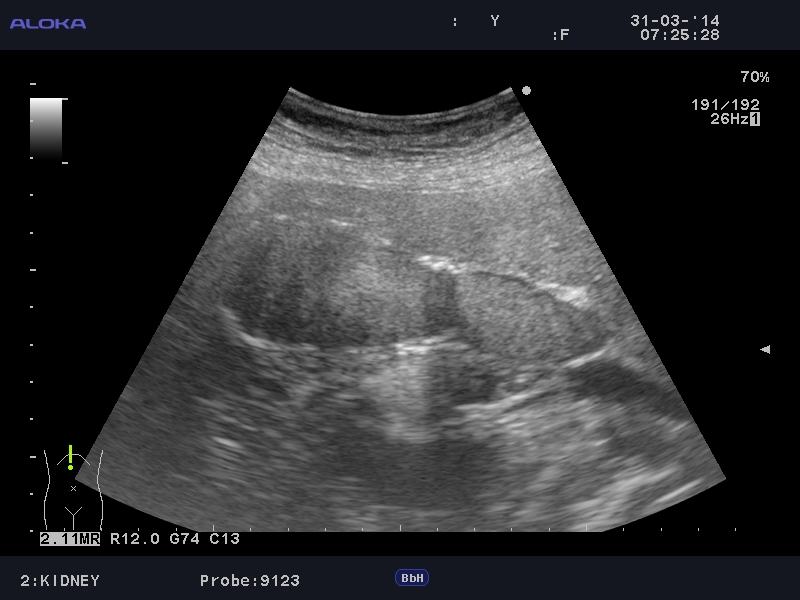

Еще случай.

Бабушка из отделения сестринского ухода, без жалоб на боли в животе. Лаб. анализы не изменены.

Если кальциноз стенки полный и содержимое пузыря осмотру не доступно, то есть показания к проведению КТ-МРТ. Если стенки инкрустированы частично (как в представленных случаях) и можно оценить характер содержимого и структуру стенок, то можно ограничиться только УЗИ. Далее, если есть подозрение на опухоль то пациента направляют к онкологу, а он сам определяет дальнейшую тактику.